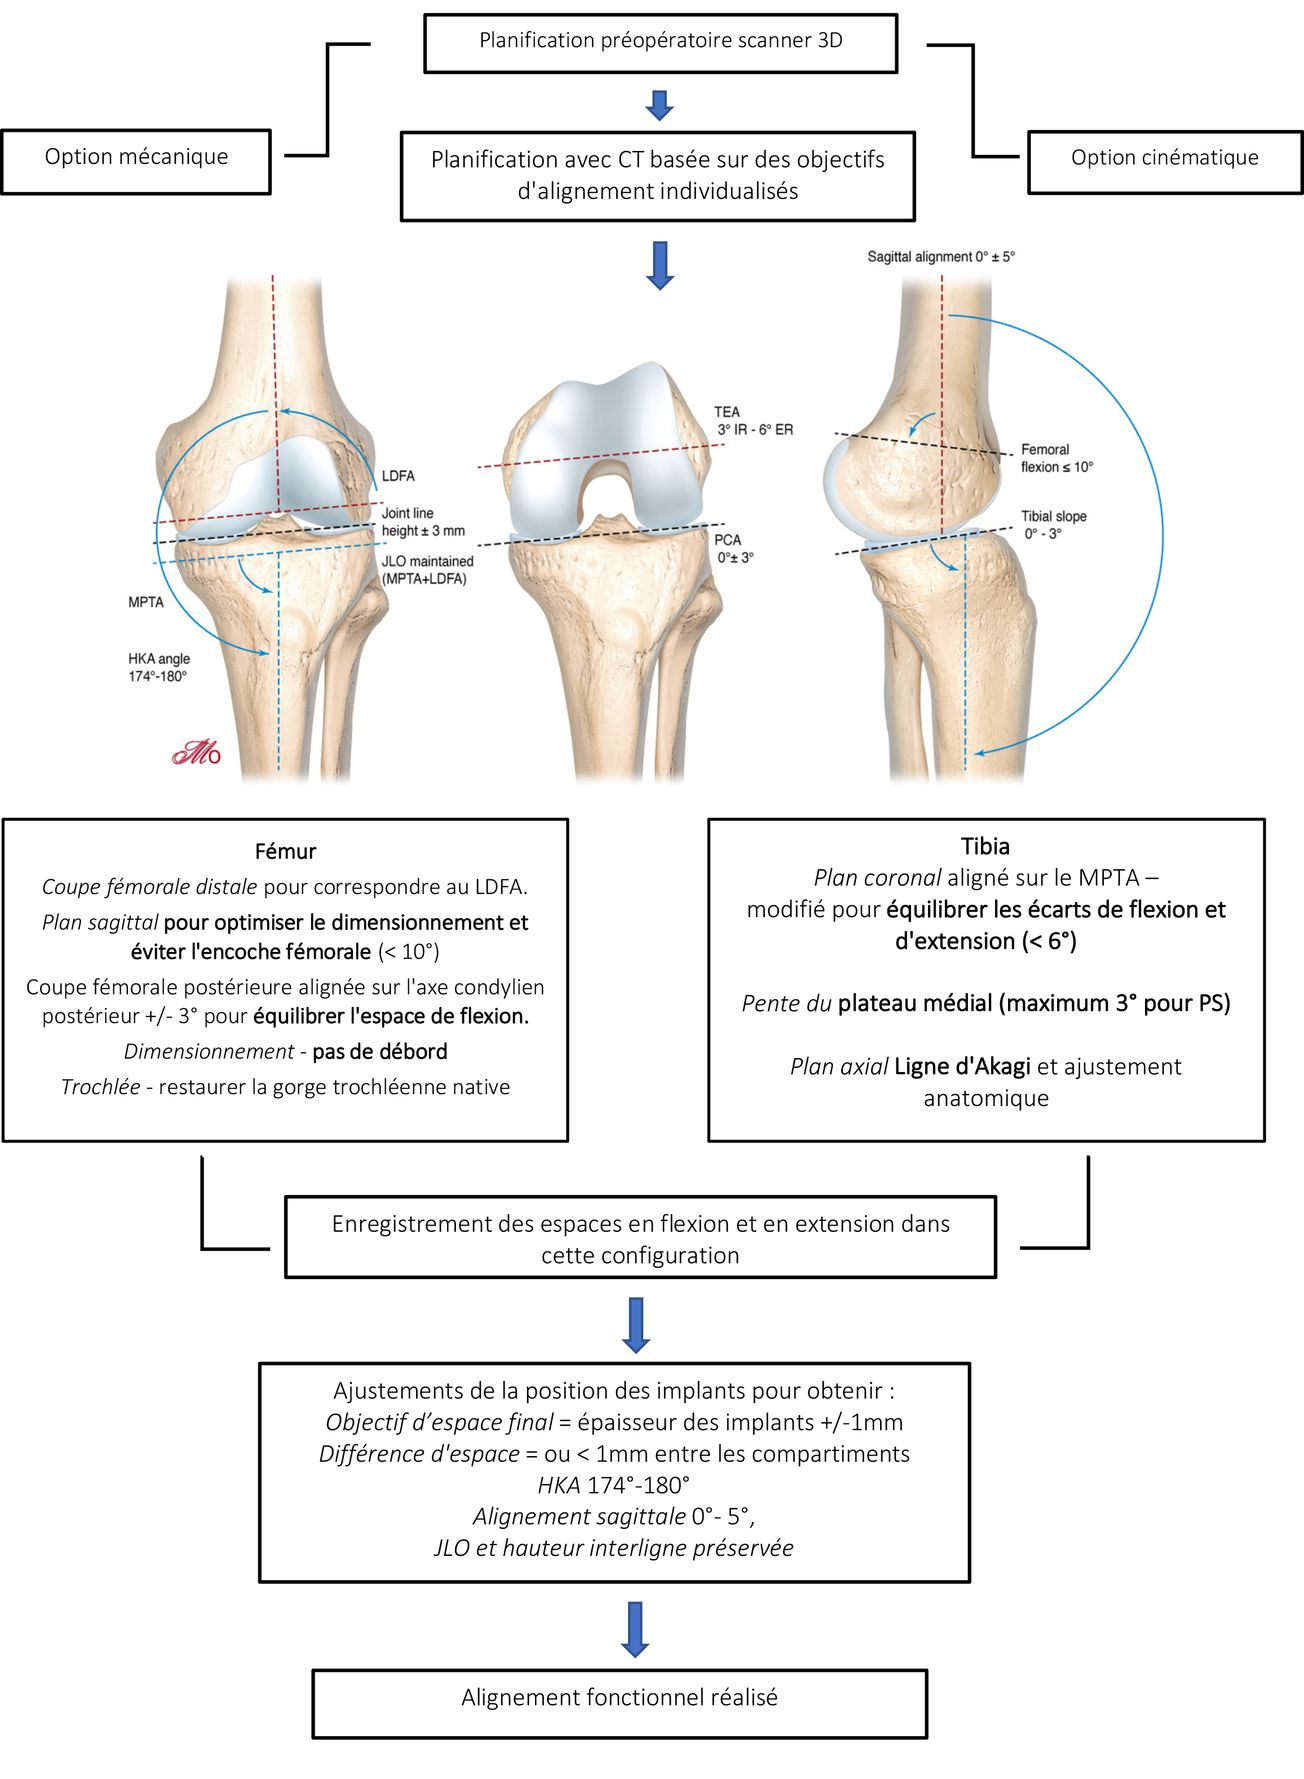

Mise au point Philosophie de l'alignement fonctionnel dans l'arthroplastie totale du genou Justification et aspects techniques pour les morphotypes en varus à l'aide d'une assistance robotique et d’une imagerie préopératoire 3D , Sébastien Lustig Hôpital de la Croix-Rousse, Centre Albert Trillat, Lyon, France , Jobe Shatrov Landmark Orthopaedics, St Leonards, Australie , Elvire Servien Hôpital de la Croix-Rousse - HCL, Service de chirurgie orthopédique et de médecine du sport, FIFA medical center of excellence, Lyon, France , Cécile Batailler Centre Albert Trillat, CHU Lyon Nord - Hôpital de la Croix Rousse, Lyon - France N°312 - Mars 2022 ● 18 min de lecture